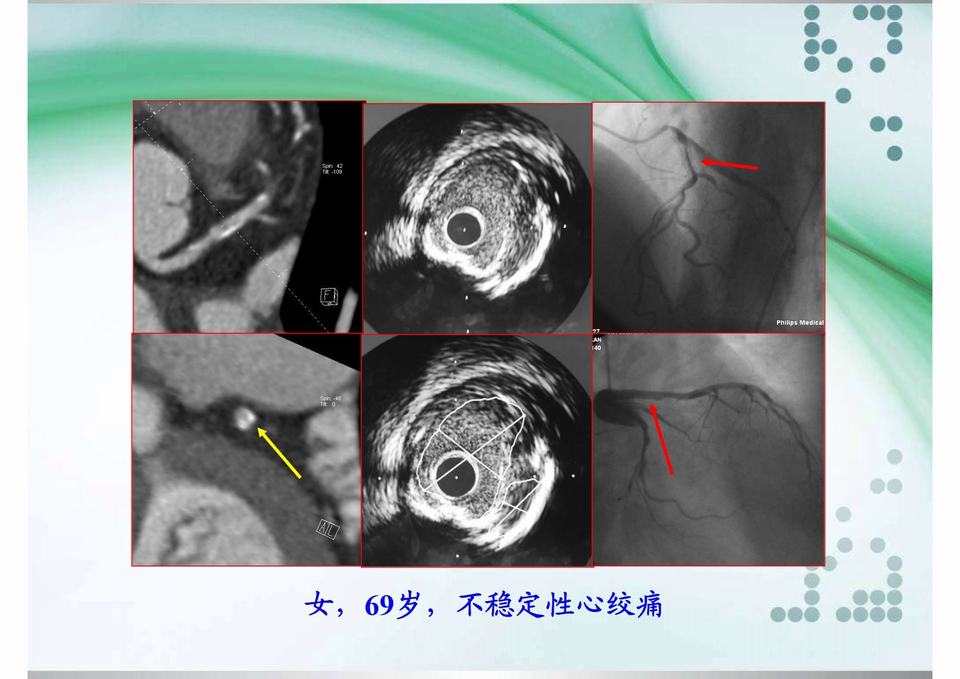

图01